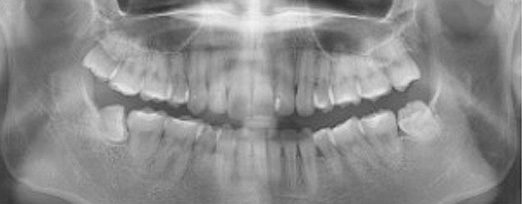

사랑니 발치

청담네오플란트는 3D CT 촬영 후 전문의료진들의 정확한 분석으로 안전하게 사랑니를 발치합니다.

청담네오플란트치과 사랑니 발치 프로세스

01. CT 촬영

안전하고 통증을 최소화한 발치를 위해 3차원 정밀 분석을 합니다.

02. 정확한 분석

사랑니의 크기와 방향, 깊이, 뿌리 상태 등과 구강검진을 실시합니다.